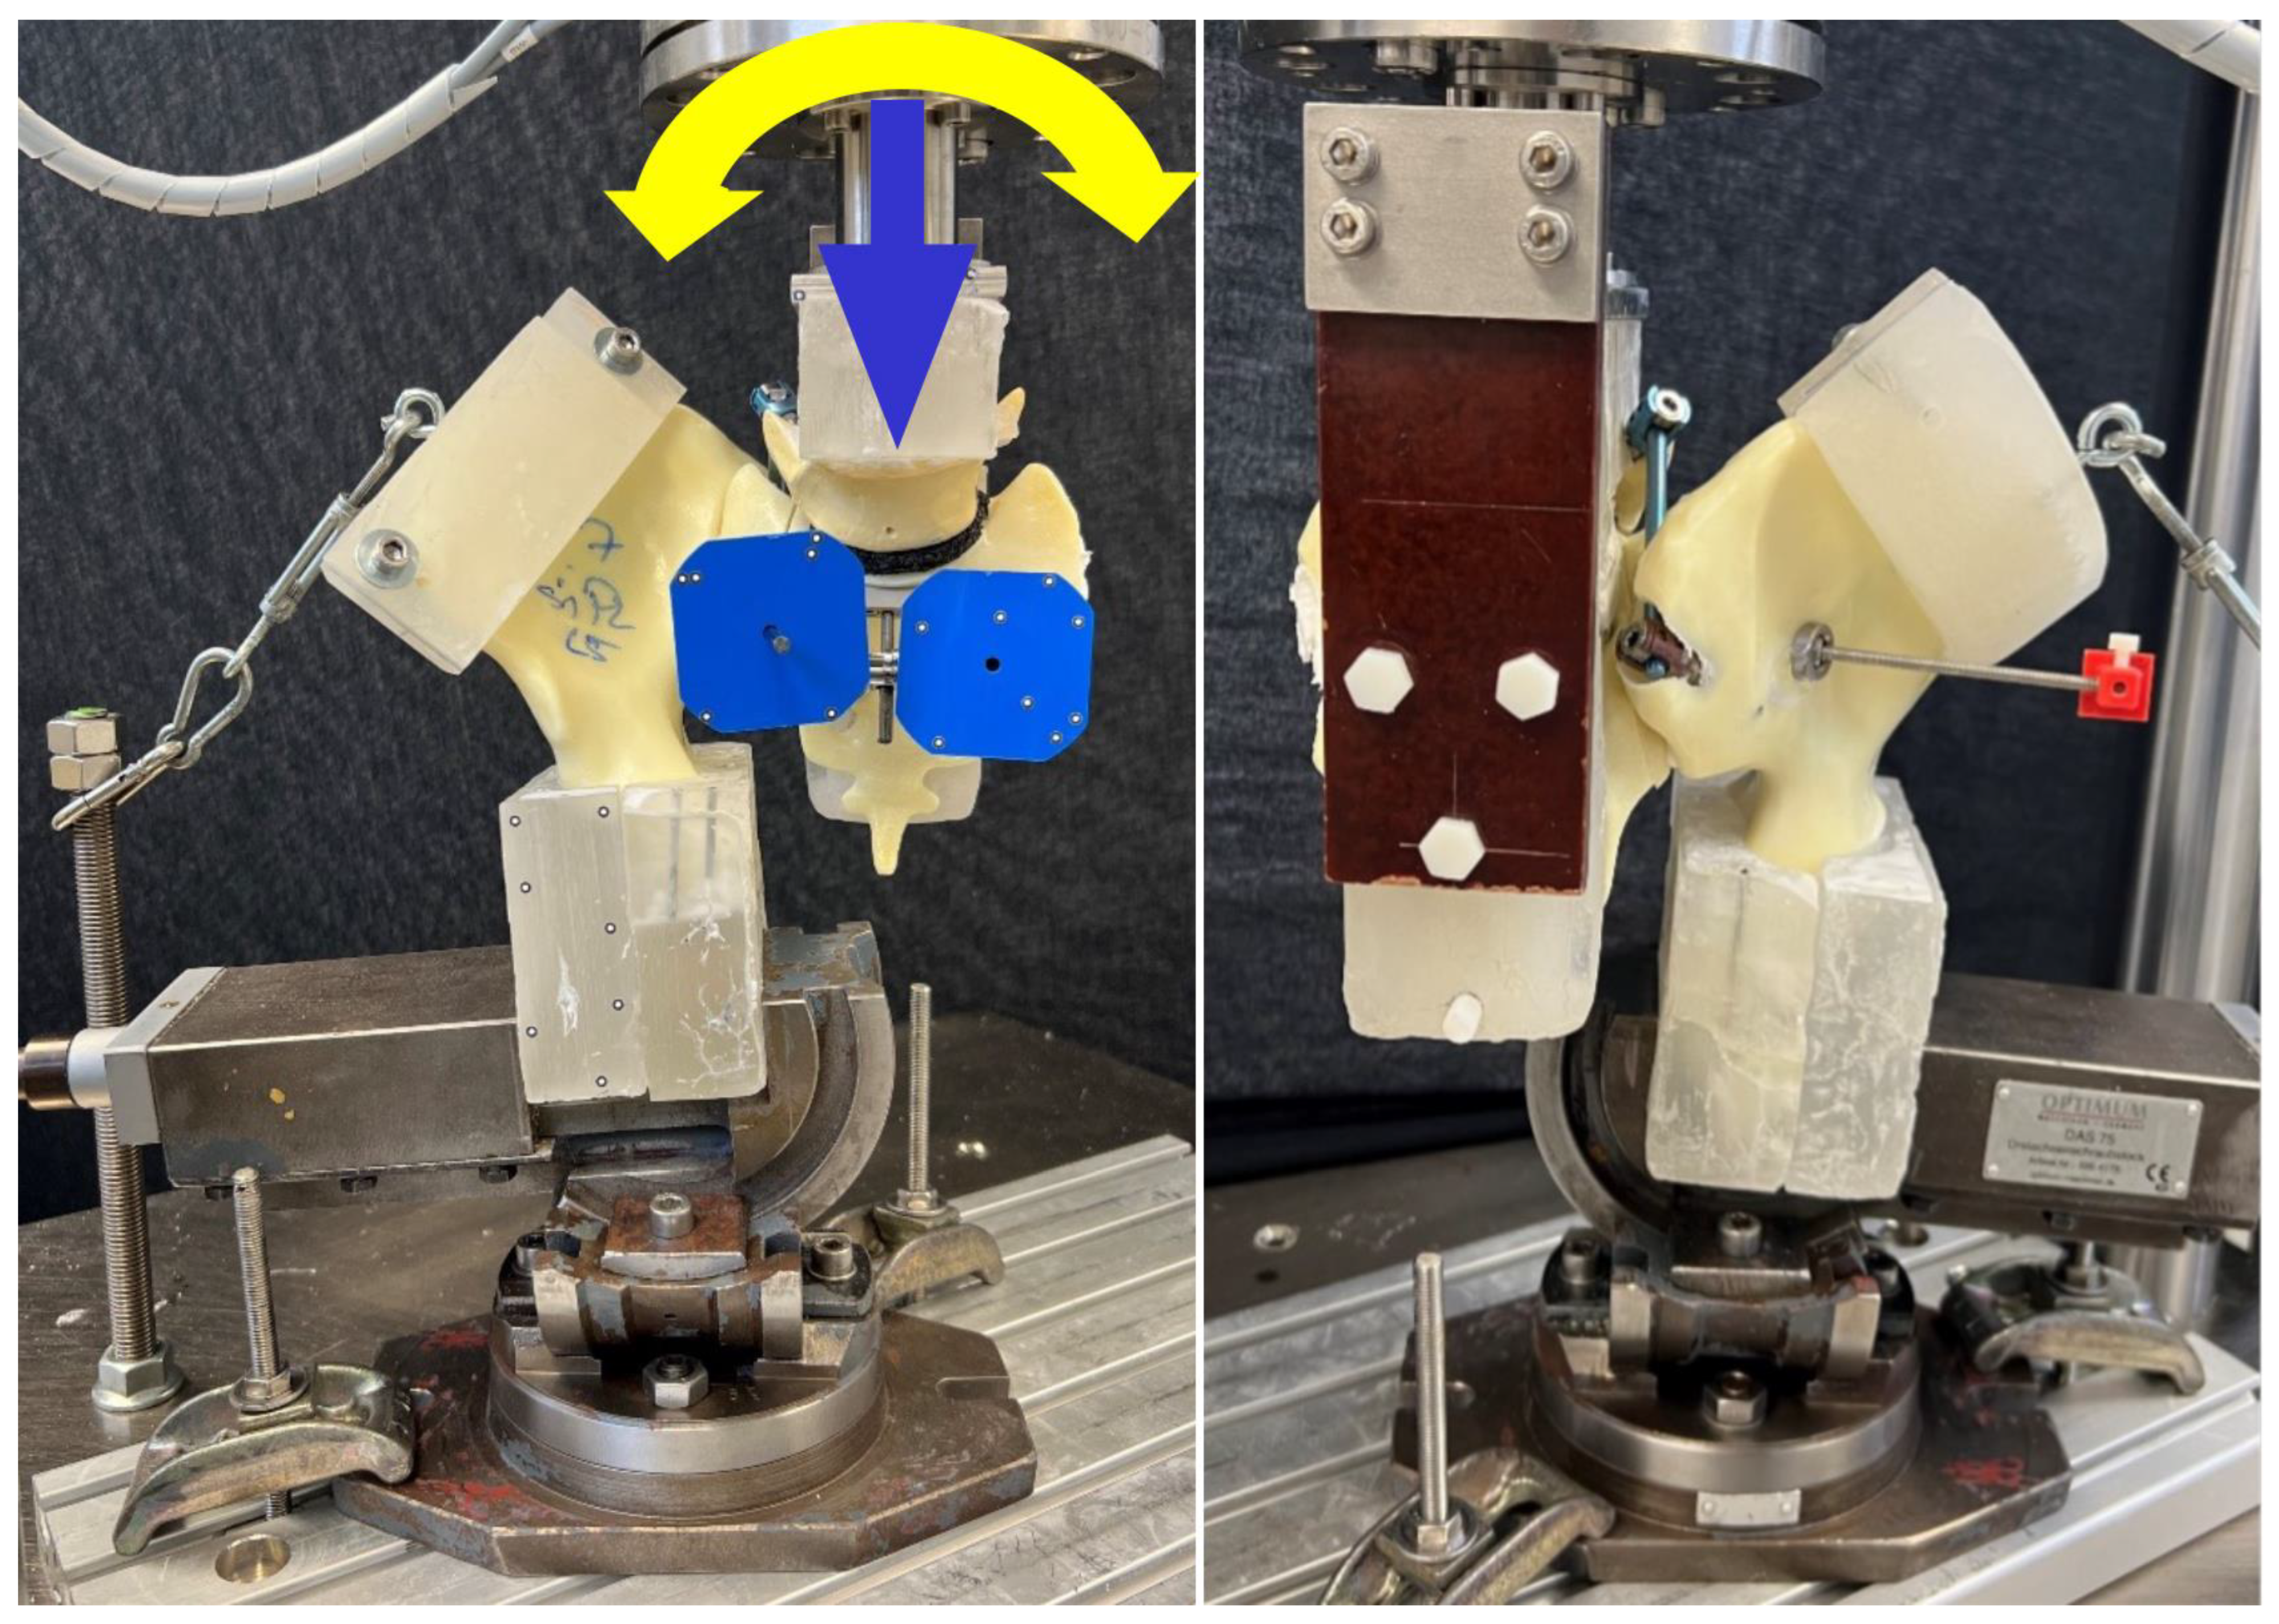

2.4. Biomechanical Testing

2.5. Data Evaluation